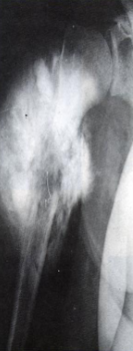

Radiography:

Large, destructive, mixed lytic & sclerotic mass with infiltrative margins

Extension through the cortex lifts periosteum→ reactive sub-periosteal bone formation → Codman triangle

Sunburst pattern of calcified osteoid

lung metastasis